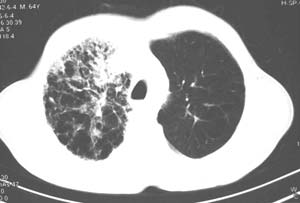

右肺上叶见片状 网格状及索条致密影.其内参杂斑点状小结节,部分融合,密度不均匀,内见含气支气管像,纵隔内见肿大淋巴结,其他肺呈代偿性肺气肿像.结合男 64  咳血,咳痰 发热 3天 血象1.2万,综合考虑:1 慢性炎症伴间质纤维化 肺气肿.2 不除外特发性感染的可能.

右肺上叶大片片状、网格状及索条致密影,前半部密实向后逐渐疏松,其内参杂斑点状小结节,密度不均匀,内见含气支气管像,纵隔内见肿大淋巴结,其他肺呈弥漫性小叶中心性性肺气肿改变,结合男 64  咳血,咳痰,发热3天,血象1.2万。考虑:1 慢性支气管炎、肺气肿合并右上肺感染。2 不除外结核合并感染的可能。

右肺上叶见片状 网格状及索条致密影.其内参杂斑点状小结节,部分融合,密度不均匀,内见含气支气管像,前段有一小片结影,纵隔内见肿大淋巴结,右侧胸腔少量积液。.结合男 64  咳血,咳痰 发热 3天 血象1.2万,综合考虑:2 右上肺感染伴间质纤维化 2 警惕细支气管肺泡癌。3建议结合临床及进一步检查[痰及纤支镜]或治疗后复查

右侧胸廓略小于左侧,右肺上叶大片实变影,近肺门处密度较高,内见支气管气相,周围较淡,呈网格状,余肺野清晰,纵隔内见肿大淋巴结,右侧胸腔少量积液。临床 咳血,咳痰 发热 , 血象1.2万。

考虑大叶性肺炎。

右侧胸阔塌陷,纵隔右移。右上肺大片状高密度影,沿支气管血管束走行,内见点状钙化;支气管充气征阳性,支气管呈柱状扩张;胸膜下小叶间隔增厚;右侧后胸壁内侧见带状水样密度影;纵隔淋巴结增大。

考虑:①右上叶陈旧性结核合并感染可能大。②右侧少量胸水。

影像学表现:右肺上叶大片状、网格状及索条致密影,前半部密实向后逐渐疏松,其内参杂斑点状小结节,密度不均匀,内见含气支气管像,纵隔内见肿大淋巴结.

综上,以右上肺tb(干酪性肺炎)首先考虑.当然大叶性肺炎不能除外.(血象不是特别高,纵隔内淋巴结肿大,也不甚支持.).如果经积极抗感染治疗,病灶明显好转.更能明确为大叶性肺炎.也不能明确排除肺ca.建议痰培养和纤支镜.

右肺上叶见片状,网格状及索条样致密影,内见支气管气相,纵隔内见肿大淋巴结,同侧胸腔内少量液性密度影,余肺呈肺气肿改变,临床:男,64岁,咳血,咳痰,发热3天,wbc---1.2万

考虑:1)右肺大叶性肺炎2)肺气肿